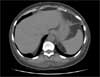

A CT scan of the abdomen with contrast performed as part of an evaluation of the chronic diarrhea revealed a Bochdalek hernia.

This congenital defect, first described by Bochdalek in 1848, is an improper fusion of the posterolateral foramina of the diaphragm that results in herniation of the abdominal organs into the chest cavity. Because the left abdominal canal closes later than the right during embryogenesis, 85% of cases involve the left side of the diaphragm.1

Bochdalek hernia occurs in about 1 of 2200 to 2500 live births and affects males twice as often as females. The defect may cause respiratory or GI symptoms at birth; however, it may remain asymptomatic. In adults, Bochdalek hernia is primarily an incidental finding on a CT scan of the abdomen, as it was in this patient. Its incidence in asymptomatic adults varies between 0.17%2 and 6%.3